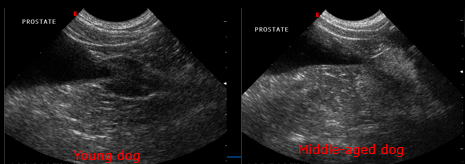

What is this?

Smooth symmetrical enlargement consistent with BPH

Less marked enlargement with irregular contrast leakage suggestive of neoplasia

What is the normal appearance of prostate ultrasound?

What is this appearance?

Immature Hypoechoic

Discuss the appearance here

Mature – hard to make out margin

Smooth and rounded

Under 2cm